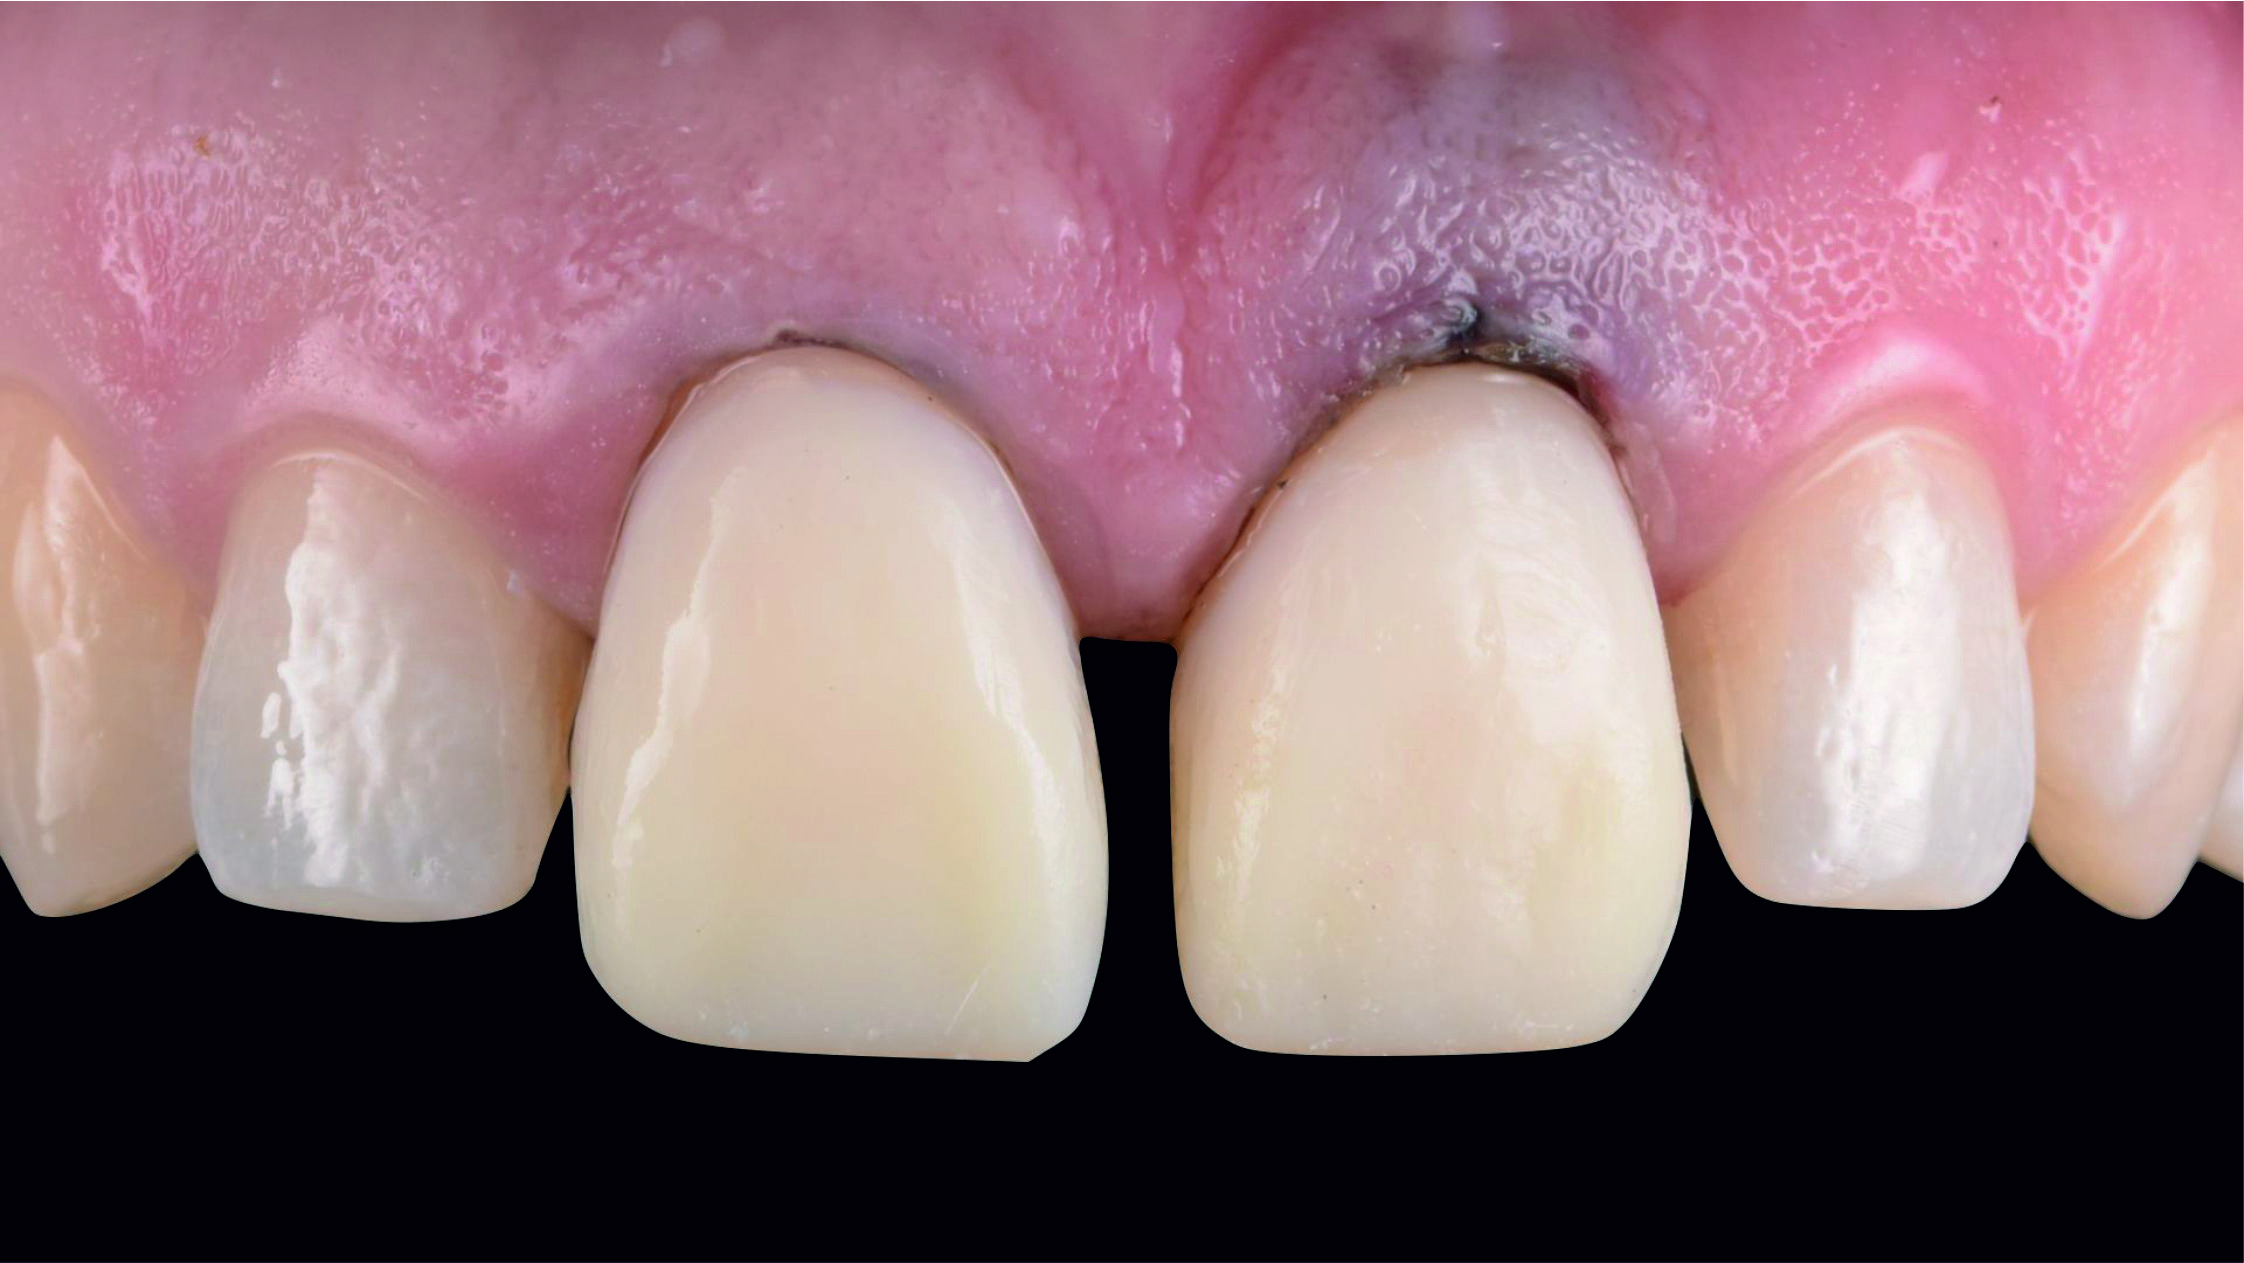

Фото 8. Після видалення штучних коронок видно, що кукси відпрепаровані з надлишком.Фото 9. Після усунення цементу, який залишився, та установки ретракційної нитки можна розглянути під’ясенну зону препарування, яка має різну глибину занурення, значно більше виражену в проксимальних ділянках кукс.

Фото 10. Проаналізувавши початкову ситуацію, можна сказати, що нам ще треба виконати низку складних маніпуляцій для препарування, встановлення тимчасових конструкцій, зняття відбитка та фіксації готових конструкцій.

Фото 11. Кукси реконструювали за допомогою композитного матеріалу і заново відпрепарували на тому ж рівні висоти шийки, на якому вони були відпрепаровані раніше.